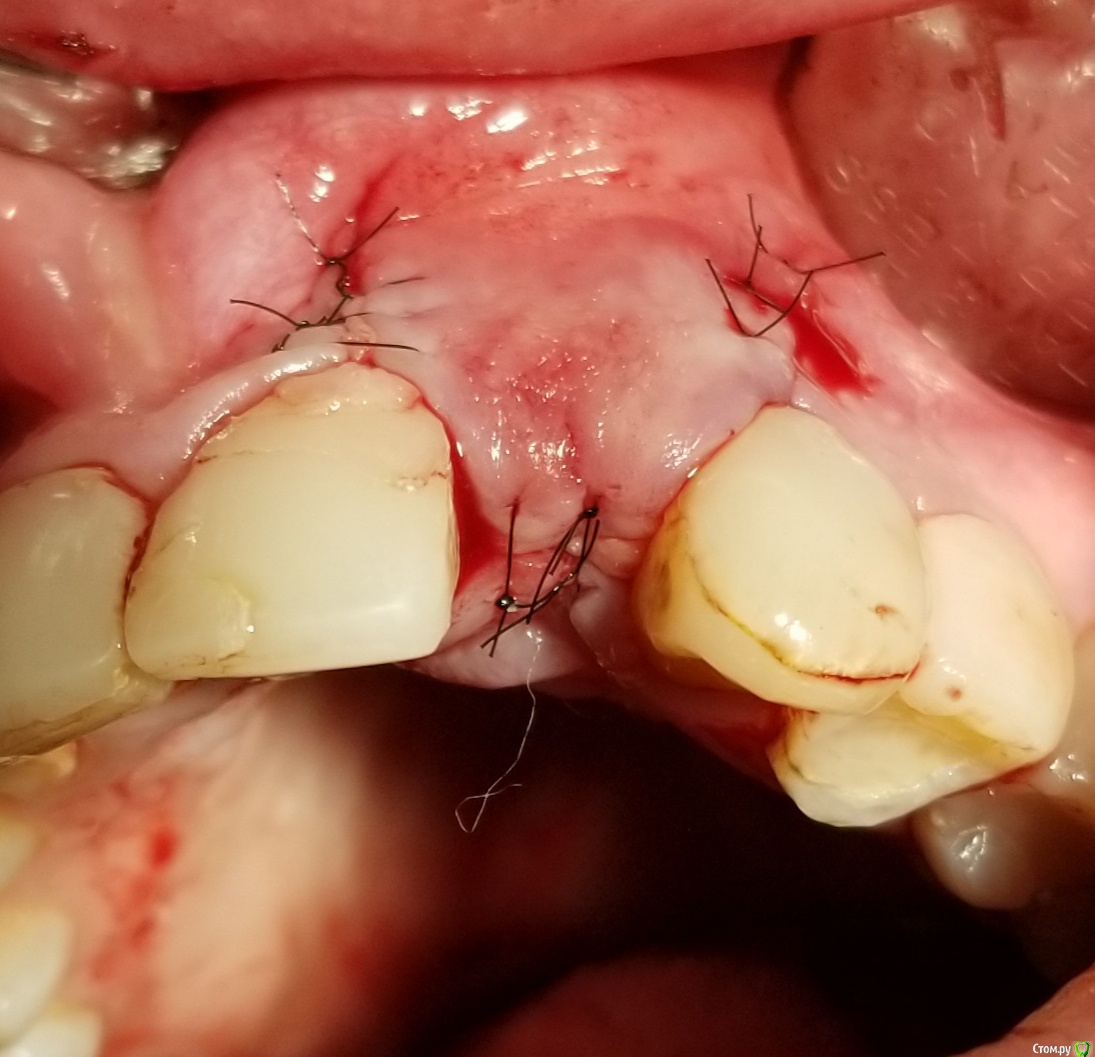

АнтонТЛТ Опубликовано 18 сентября, 2018 Поделиться Опубликовано 18 сентября, 2018 У шейки недопаковано было, апикальной лучше фиксировать, вертикальные разрезы надо не так делать. Спейсер неродной что ли? 6 Ссылка на комментарий

Bier Опубликовано 19 сентября, 2018 Поделиться Опубликовано 19 сентября, 2018 какой апатос был? кортикал или микс? Апикальная фиксация обязательна. По всем пунктам согласен с Антоном.Вертикальные разрезы ужасные. Надо резать через центр сосочка, ни в коем случае нельзя по зениту разрезать. 1 Ссылка на комментарий

L.E.S.I.K. Опубликовано 19 сентября, 2018 Поделиться Опубликовано 19 сентября, 2018 (изменено) апатос микс.почему нельзя резать по зениту?из-за рубцов в эстетически значимой зоне?Можно рецессию получить. На картинке нарисовано какНЕ надо делать.Новый точечный рисунок.bmp Изменено 19 сентября, 2018 пользователем L.E.S.I.K. 1 Ссылка на комментарий

Kostoprav Опубликовано 19 сентября, 2018 Автор Поделиться Опубликовано 19 сентября, 2018 (изменено) сегодня установил фдм, десна и вправду на центральном немного задралась, уложил 2 сочных сст под лоскут. Больше разрез через зенит делать не буду. Спасибо всем за советы! Изменено 19 сентября, 2018 пользователем Kostoprav Ссылка на комментарий

an_ver Опубликовано 29 сентября, 2018 Поделиться Опубликовано 29 сентября, 2018 У шейки недопаковано было, апикальной лучше фиксировать, вертикальные разрезы надо не так делать. Спейсер неродной что ли?При таком виде верт.разрезов практически всегда ресессия обеспечена Ссылка на комментарий